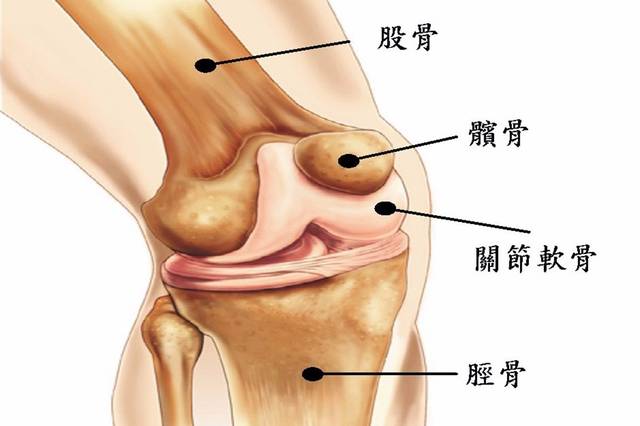

膝关节内侧疼痛的常见原因及处理方法

膝关节内侧疼痛的常见原因及处理方法

膝关节是人体最大、最复杂的关节,也是跑步中伤病出现最繁多的部位。单是膝内侧疼痛就包括了内侧副韧带损伤、鹅足肌腱损伤、内侧半月板损伤